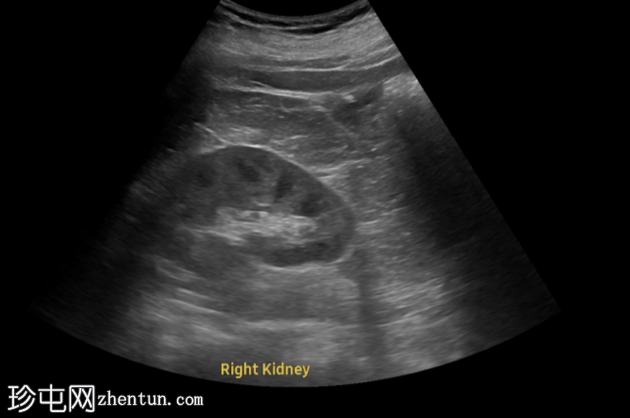

超声

检查

超声显示左侧轻度肾积水,由膀胱输尿管连接处一枚7毫米的远端输尿管结石阻塞所致,输尿管射流正常。

肾积水并非总是由输尿管结石引起。肾盂和肾盏扩张的程度与结石大小并不一定相关。

较小的结石有时可导致中度上游扩张,而较大的结石可能仅引起轻微的充盈感,这取决于患者的引流和水合状态。